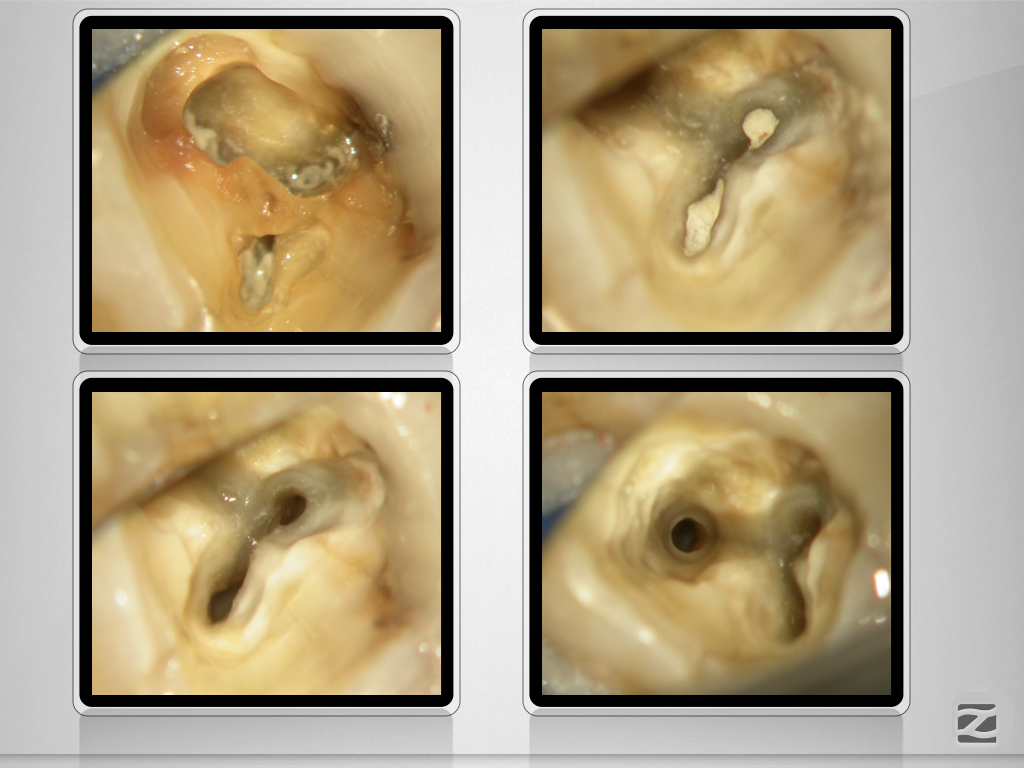

37D.005

Geometrische Herausforderung